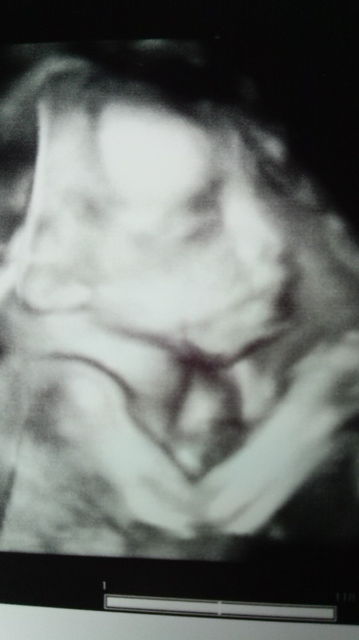

本日21w2dの次男坊

推定体重は498gでした

ちなみに22w3dの秀敏

推定体重616g

なんだか似てるぞ…またしても父ちゃん似なのか